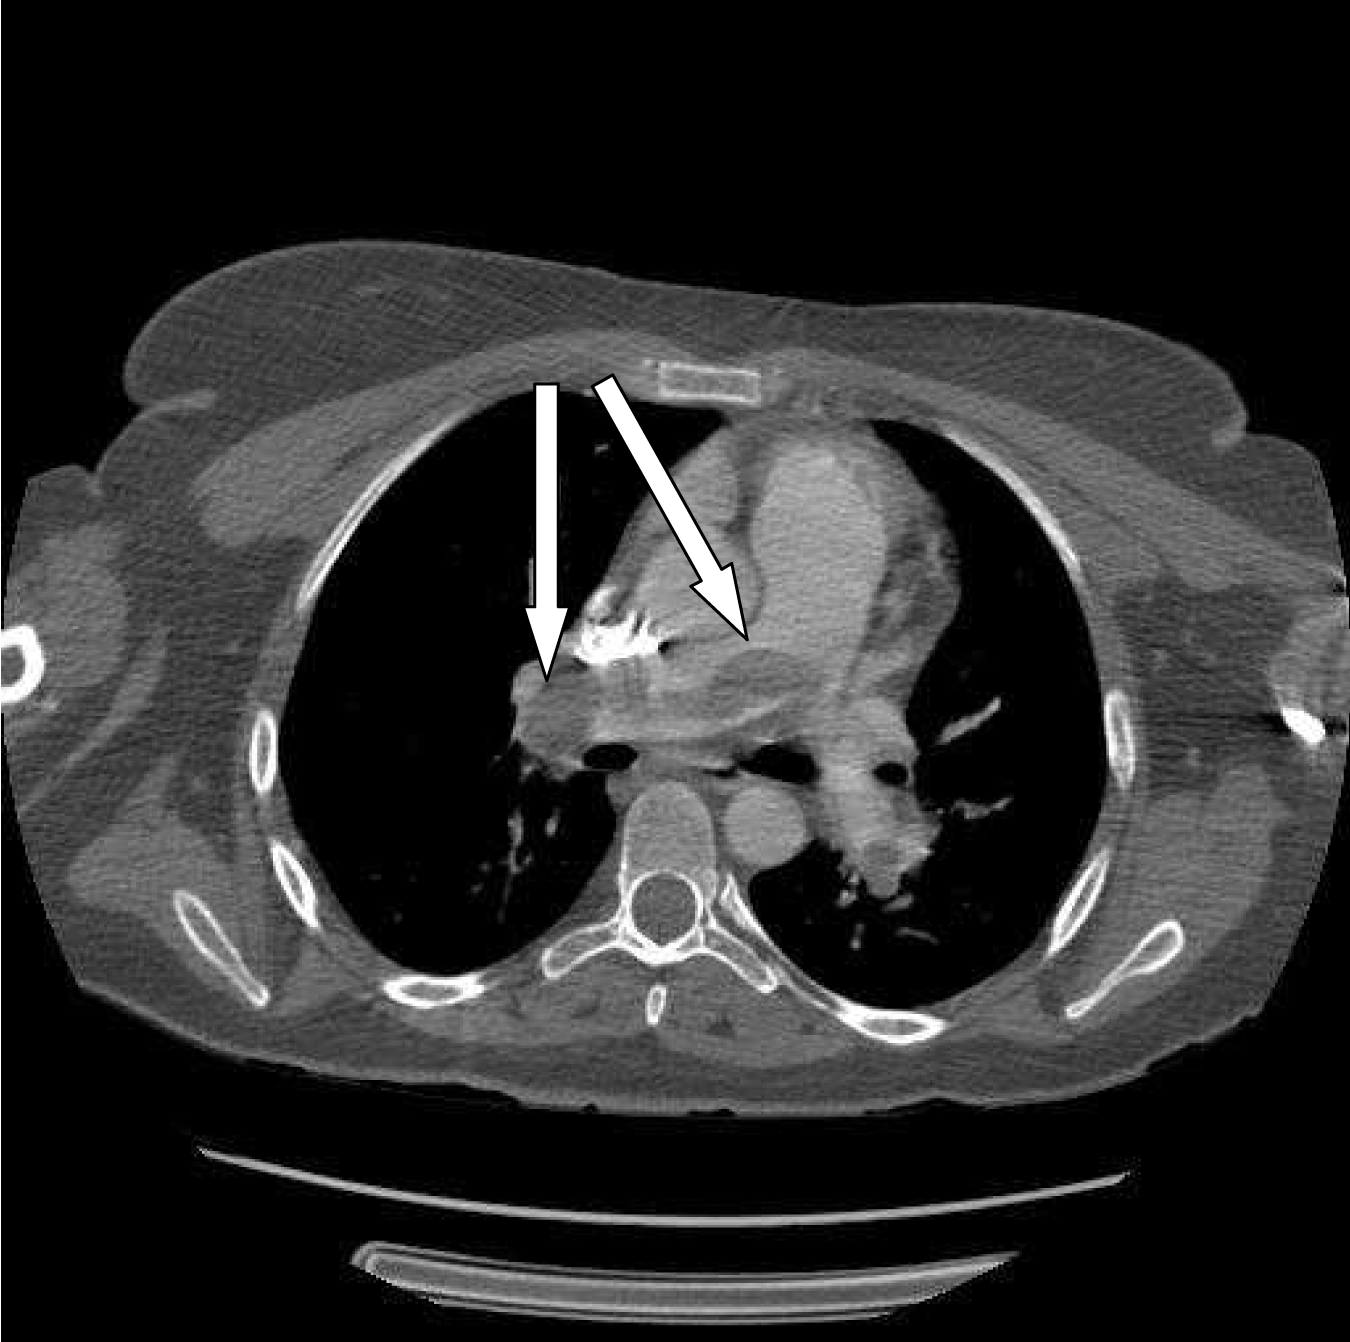

Review of the CT images obtained moments before showed a large central pulmonary embolism. (Figure 1). A heparin drip was initiated and consent was obtained for systemic fibrinolysis. Tenecteplase 45mg (0.5 mg/kg) was administered intravenously.

Figure 1: Computed tomography scan image demonstrating bilateral large central pulmonary embolism (arrows).